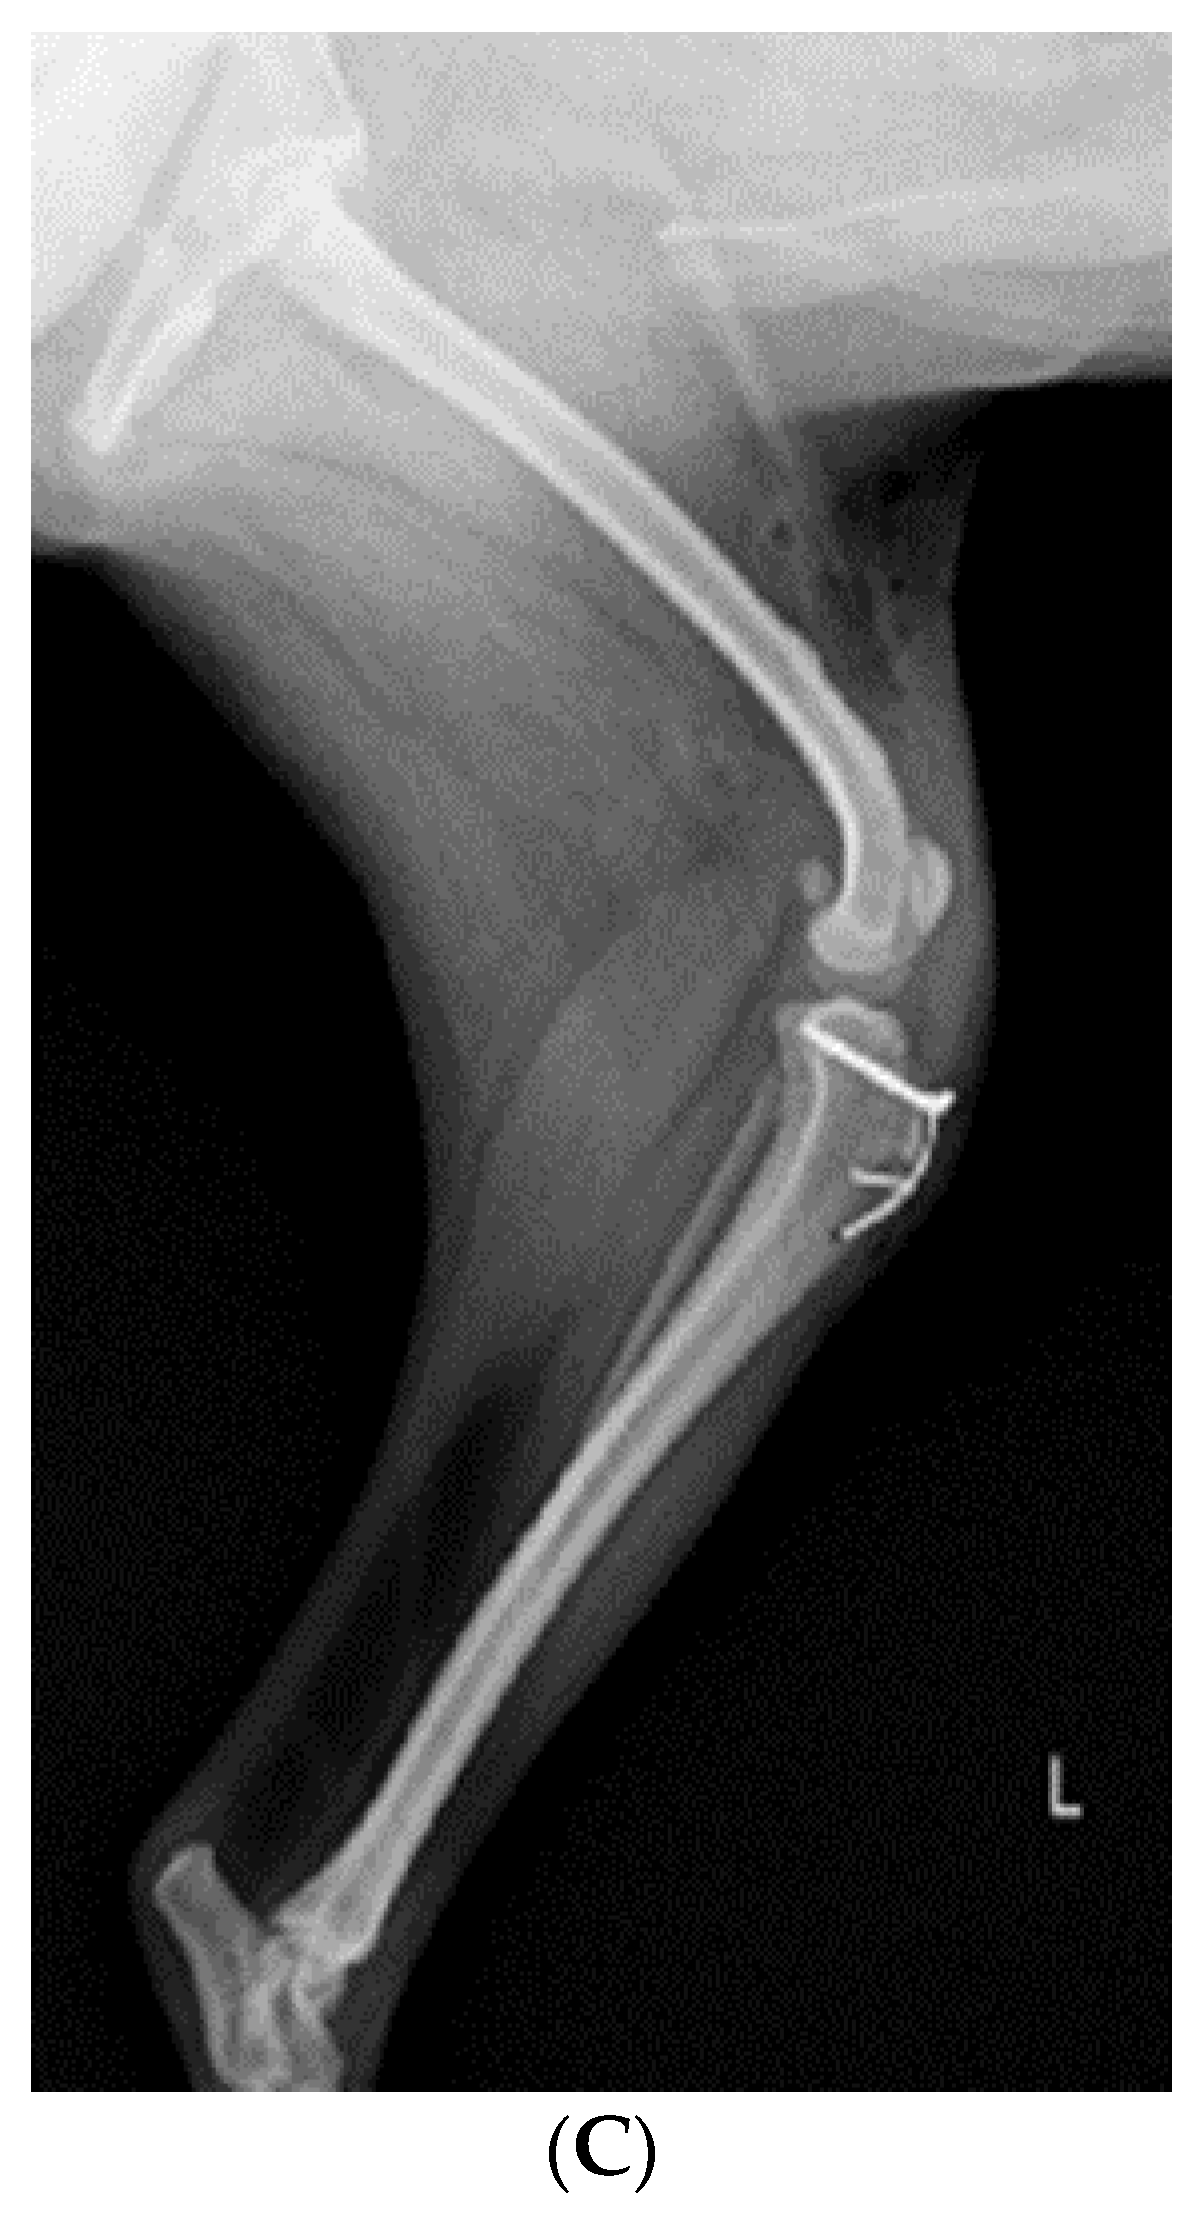

X-ray (E7239X, TOSHIBA, Tokyo, Japan) analysis was conducted. According to radiograph imaging (Weview pacs system, Seoul, Republic of Korea), the screw fixing the bone fragment to the tibial tubercle in the right hind limb had remained, and the patella was not recognized in the radiography view, which was consistent with the results following palpation (Figure 1A,B). Bone proliferation was noted, and edema was observed around the stifle joint (Figure 1A,B). Severe MPL, periostitis, and edema around the stifle joint in the left hind limb were observed (Figure 1A,C). Following a physical examination, complete blood count (Procyte Dx analyzer, Maine, USA) and biochemistry device (Catalyst One chemistry analyzer, Maine, USA) were measured. Neutrophil levels were observed to be slightly increased, namely, 11.71 μL (78.2%), suggesting that inflammatory responses were in progress (Table 1).

Figure 1.

A 2-year-old Pomeranian dog with chronic weight-bearing lameness of the stifle joints in both hind limbs. (A) Craniocaudal radiographic views of the stifle joints of the dog. (B) Lateral radiographic views of the right stifle joints. (C) Medial radiographic views of the left stifle joints. a: osteophyte, b: periostitis, c: residual screw for tibial tuberosity transposition, d: periostitis, R: right, and L: left.